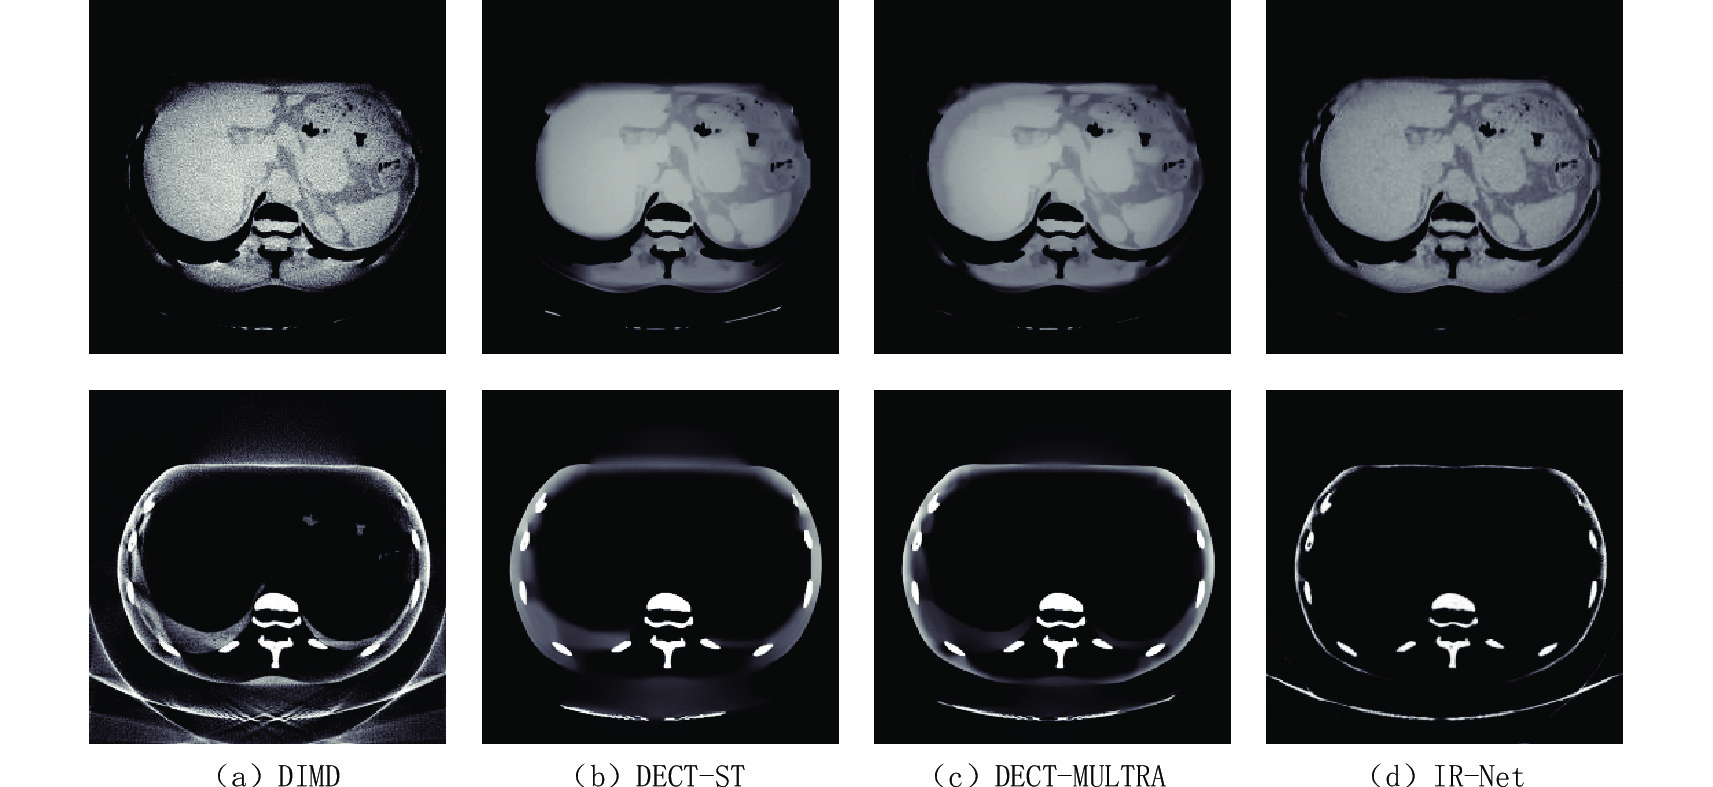

为进一步验证IR-Net网络的实用性,采用直接分解做初始迭代点,各类算法对临床腹部数据进行比较。图4显示了腹部数据的高低能图像和对比分解基材料图像,软组织和骨的显示窗口分别为[0.5 1.5] g/cm-3和[0 0.8] g/cm-3。

腹部数据添加了泊松噪声,相对于XCAT模体数据的噪声水平更高。为了适用于临床图像,网络应具有较好鲁棒性,本实验选择以软组织和骨作基材料。由图5可得DIMD获得的基图像含噪声最多;DECT-ST和DECT-MULTRA减少了噪声,但是图像过于平滑,导致一些图像细节的缺失;IR-Net网络降噪能力明显强于前3种,去除了一些较强的噪声,同时保护了图像的结构和边缘信息。总之,IR-Net网络能够抑制图像噪声,提高材料分解精度。